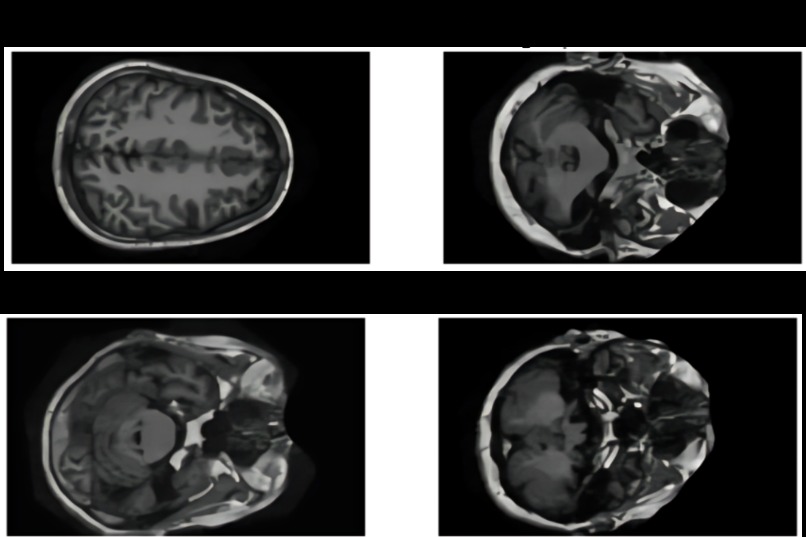

Sample images